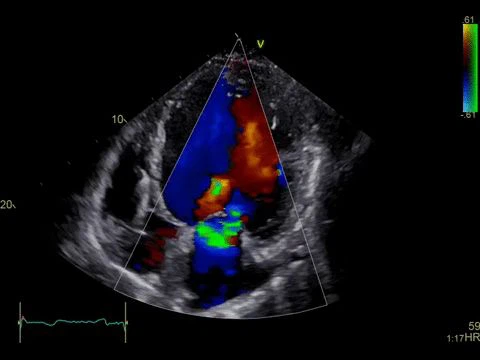

رنگین ڈوپلر الٹراساؤنڈ خون کے بہاؤ کو ظاہر کرنے کے لیے استعمال کیا جاتا ہے۔ یہ خون کے بہاؤ کی سمت اور رفتار کو ظاہر کرنے کے لیے مختلف رنگوں اور چمک کا استعمال کرتا ہے، جس سے ہمیں خون کی شریانوں اور دل کا مشاہدہ کرنے میں مدد ملتی ہے۔